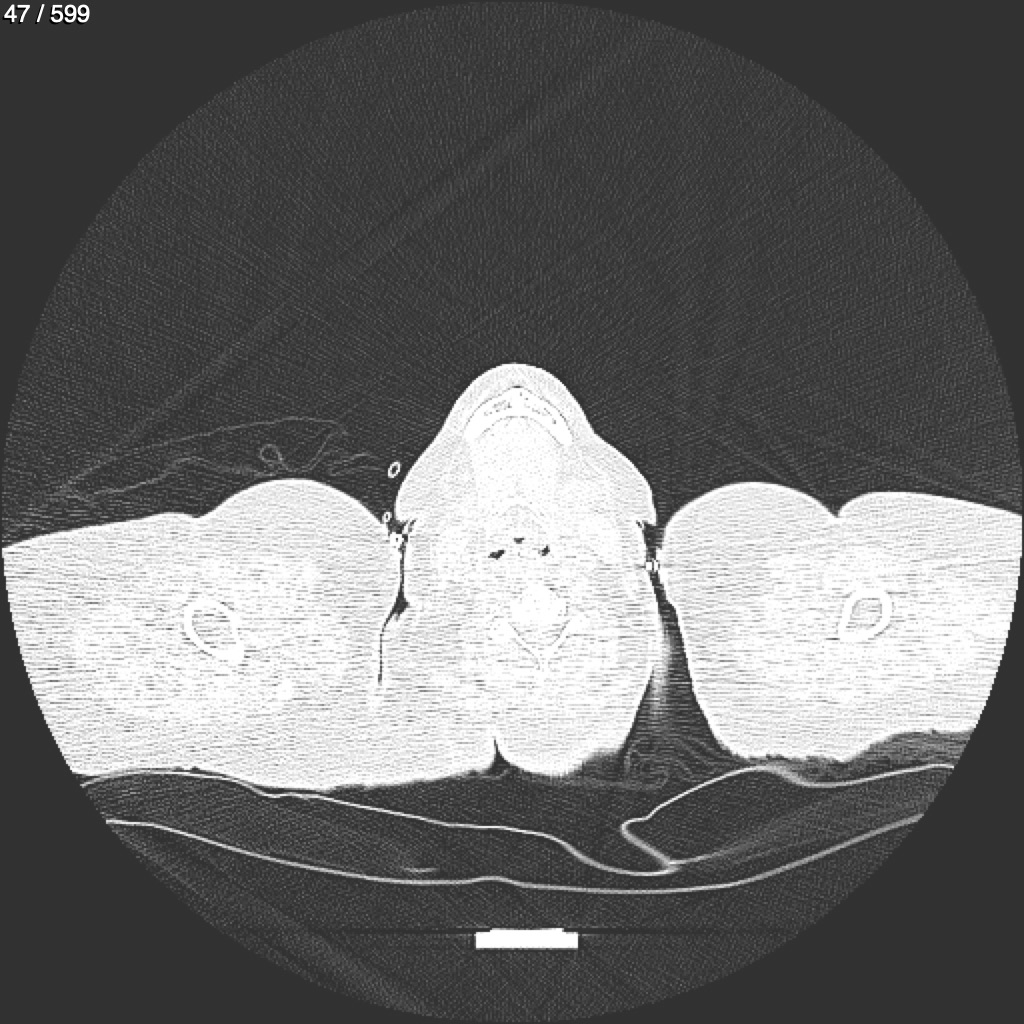

Home G​l​o​r​i​a​ ​G​l​a​d​y​s​ ​B​e​a​s​l​e​y​ ​-​ ​T​ó​r​a​x​ ​T​o​r​a​x​_​S​i​m​p​l​e​ ​(​A​d​u​l​t​o​)